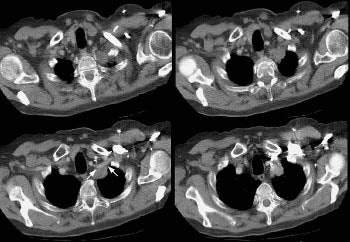

Example 1: This is an example of a superior sulcus tumor. The relationship of the lesion to the left subclavian artery is nicely demonstrated (white arrows).

.

NOTE: To load a higher resolution view, simply click directly on the image